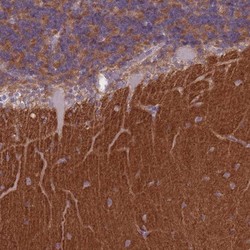

Immunohistochemistry

NBP2-48980 IHC

Full details